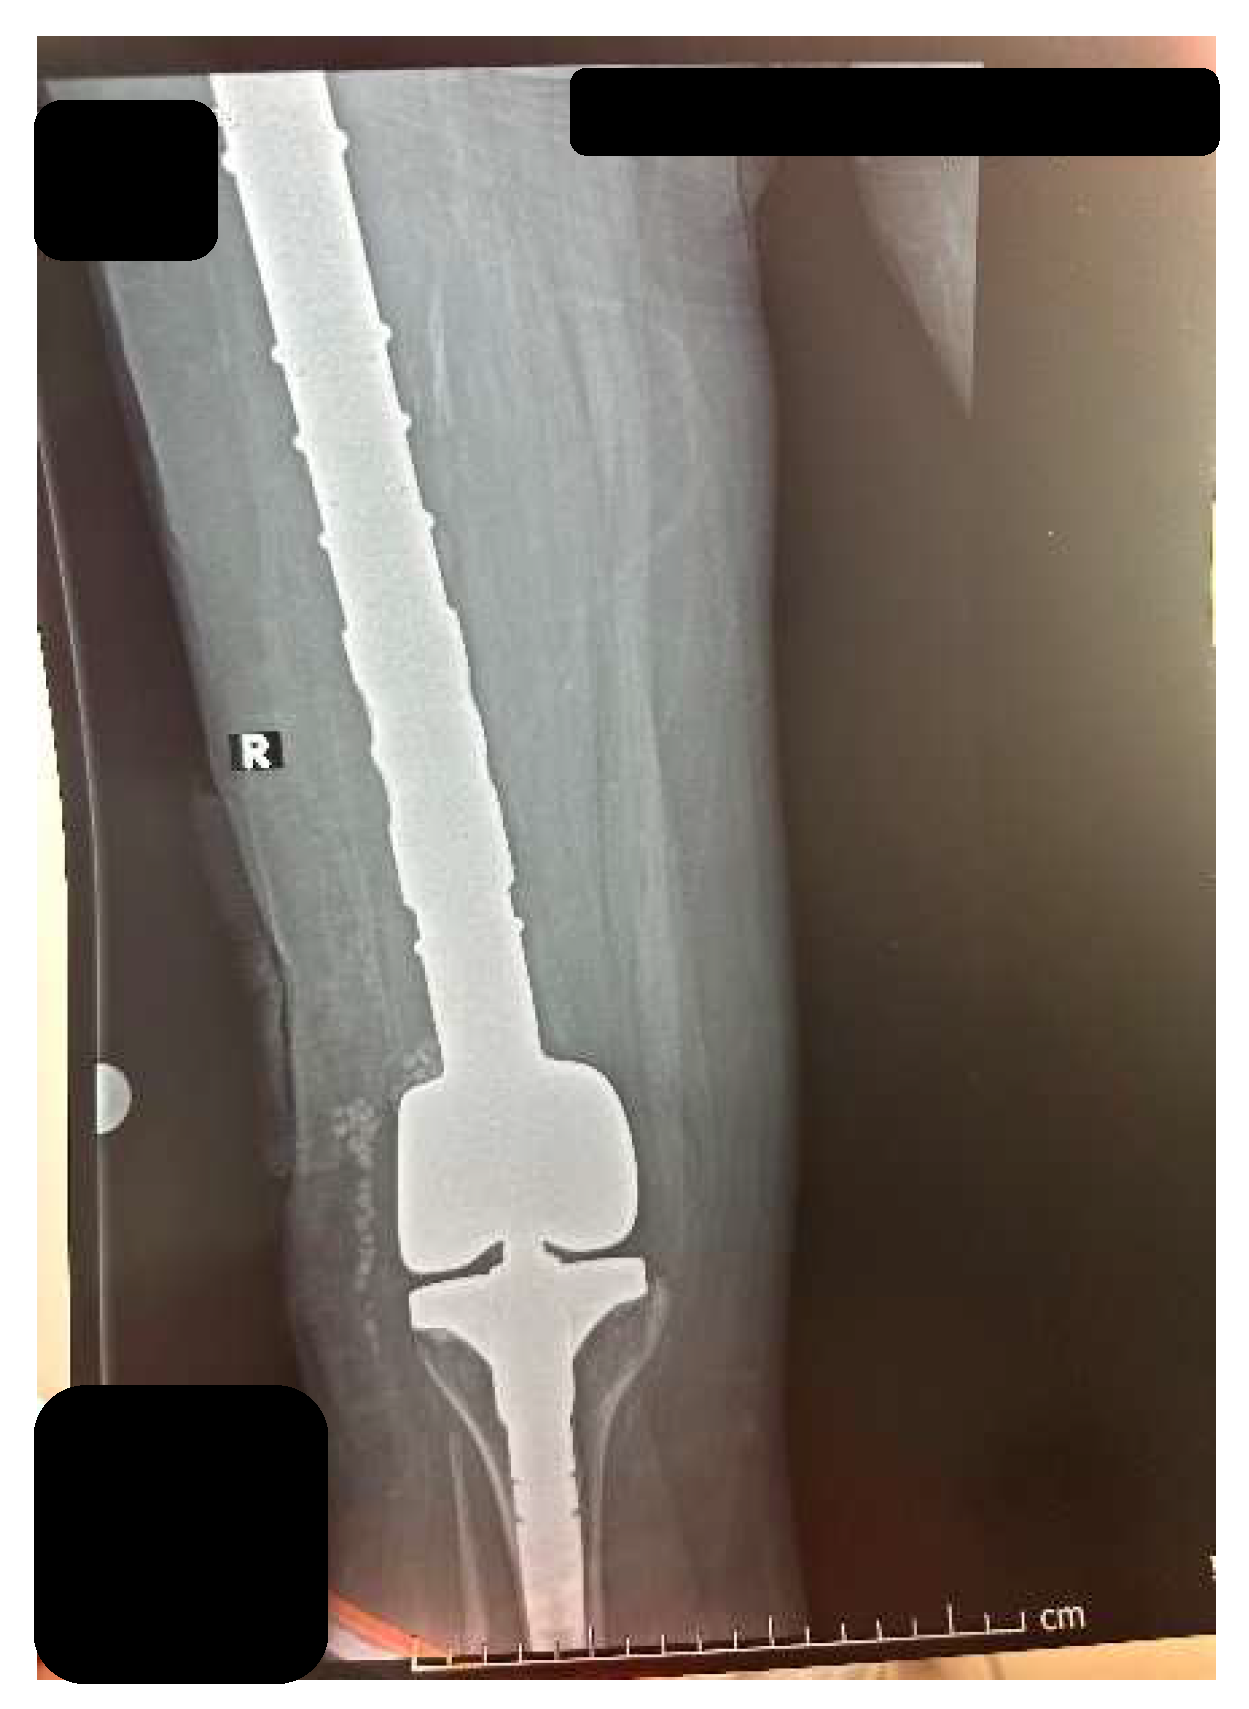

2.1. CASE 1

2.2. CASE 2